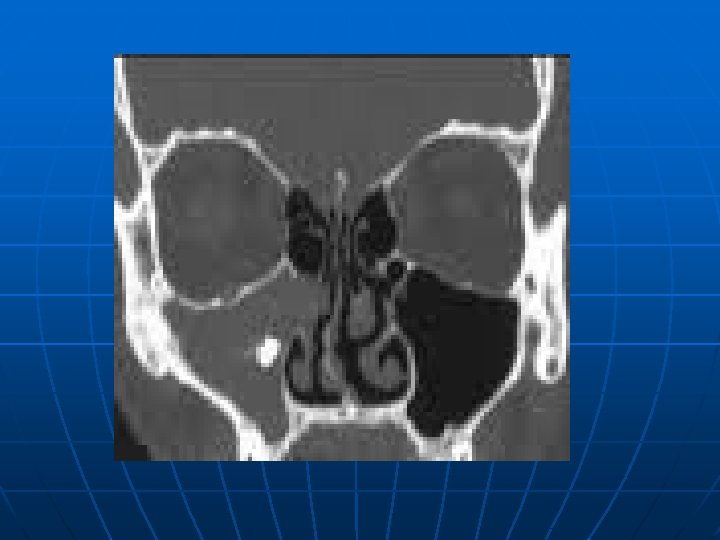

Viêm xoang n n Viêm mũi xoang là thông thường ở bệnh nhân nhiễm HIV, với báo cáo phổ biến từ 20 -68%. Lý do những bệnh nhân này quá dễ xảy ra nhiễm trùng là không hoàn toàn rõ ràng, nhưng thay đổi ở tế bào lông chuyển, cơ chế bảo vệ tại chổ cơ bản cho xoang, thì đã được báo cáo. [7] Bệnh nhân nhiễm HIV dường như có tỷ lệ cao hơn của S. aureus và P aerginosa nuôi cấy từ bệnh nhân với viêm xoang cấp và mạn tính, thường liên quan với vi khuẩn kỵ khí.

n n n P. aeruginosa , là mầm bệnh không thường gặp ở bệnh nhân miễn dịch tốt, chiếm khoảng lên tới 17% của viêm xoang cấp và 20% của viêm xoang mạn ở số dân nhiễm HIV. [5] Báo cáo đã mô tả viêm xoang do nấm với Alternaria alternata, Aspergillus, Pseudallescheria boydii, Cryptococcus, and Candida albicans. Báo cáo trường hợp đáng quan tâm khác mô tả viêm xoang gây nên bởi sinh vật đơn bào Acanthamoeba castellani